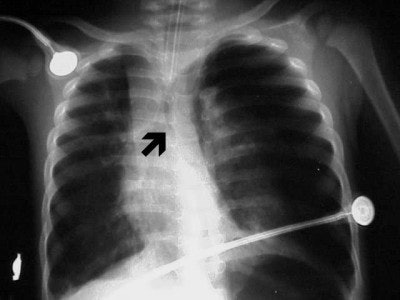

![]() |

| Figure 7 |

| Figure 8 |

In figure 6 we have a 24-month-old who has been intubated, with a diagnosis of RSV. The film is slightly overpenetrated as we cannot clearly make out lung markings, but we can see the bronchial air shadow and the tip of the ETT (marker arrow), which is right at the carina (the bifurcation of the right and left mainstem bronchus). Doctors attempted to re-position the ETT and the left lung is ruptured causing a tension pneumothorax (arrow, figure 7).